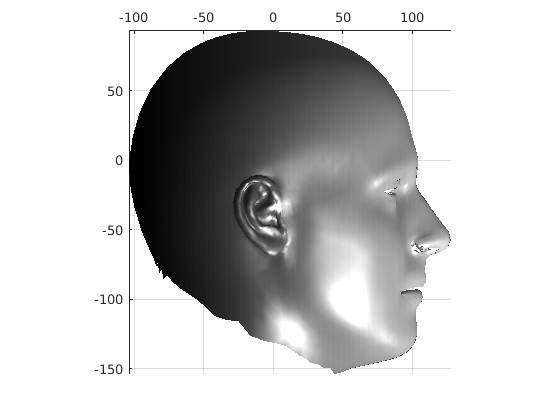

Following this, OSNR ICP iterates over a set of decreasing mesh stiffnesses (typically 10), until the registration between the template and the scan is below some error or a maximum number of iterations is reached. Figure 28 shows a selection of template warp results. The template appears to be accurately warped onto the scan, at least in the normal direction of the surfaces, it is not possible to see error tangential to the surface. Furthermore, we have noted errors on some scans on the ears. To improve these we need a method of automatically landmarking the ears, which is an area for further work.

|

|

|

|

|

|

|

|

The first two modes of head variation are shown in figures 29 and 30. These include the cranial height / facial angle mode and the (almost) pure size mode, as seen in the sagittal profile model.